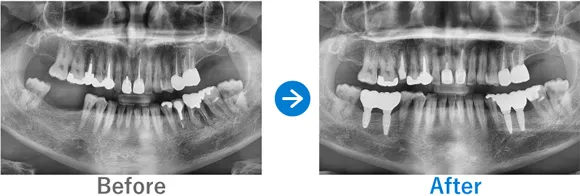

Case3

膿が溜まった奥歯を抜歯しインプラントに。埋もれていた親知らずも抜歯

右下6に歯根嚢胞あり、かかりつけ医院で抜歯が必要と診断

インプラント1本:右下6、抜歯ソケットプリザベーション

495,000円(内訳:抜歯ソケットプリザベーション、インプラント1本(ストローマン)、ガイド、仮歯、保証20年)

来院の背景

右下の治療済みの歯の根っこに膿が溜まり、かかりつけの歯科医院で抜歯が必要と言われて来院されました。

治療結果

歯根の先端に膿ができており、骨吸収が大きい状態でした。そこで、抜歯時に膿をきれいに取り除いたうえで骨補填を行いました。抜歯ソケットプリザベーションからインプラントを行うことにより、歯茎が痩せることなくインプラントを埋入できました。患者様からは、しっかりと噛めるようになったと喜んでいただきました。また、インプラントに加えて埋伏していた親知らずの抜歯も行いました。